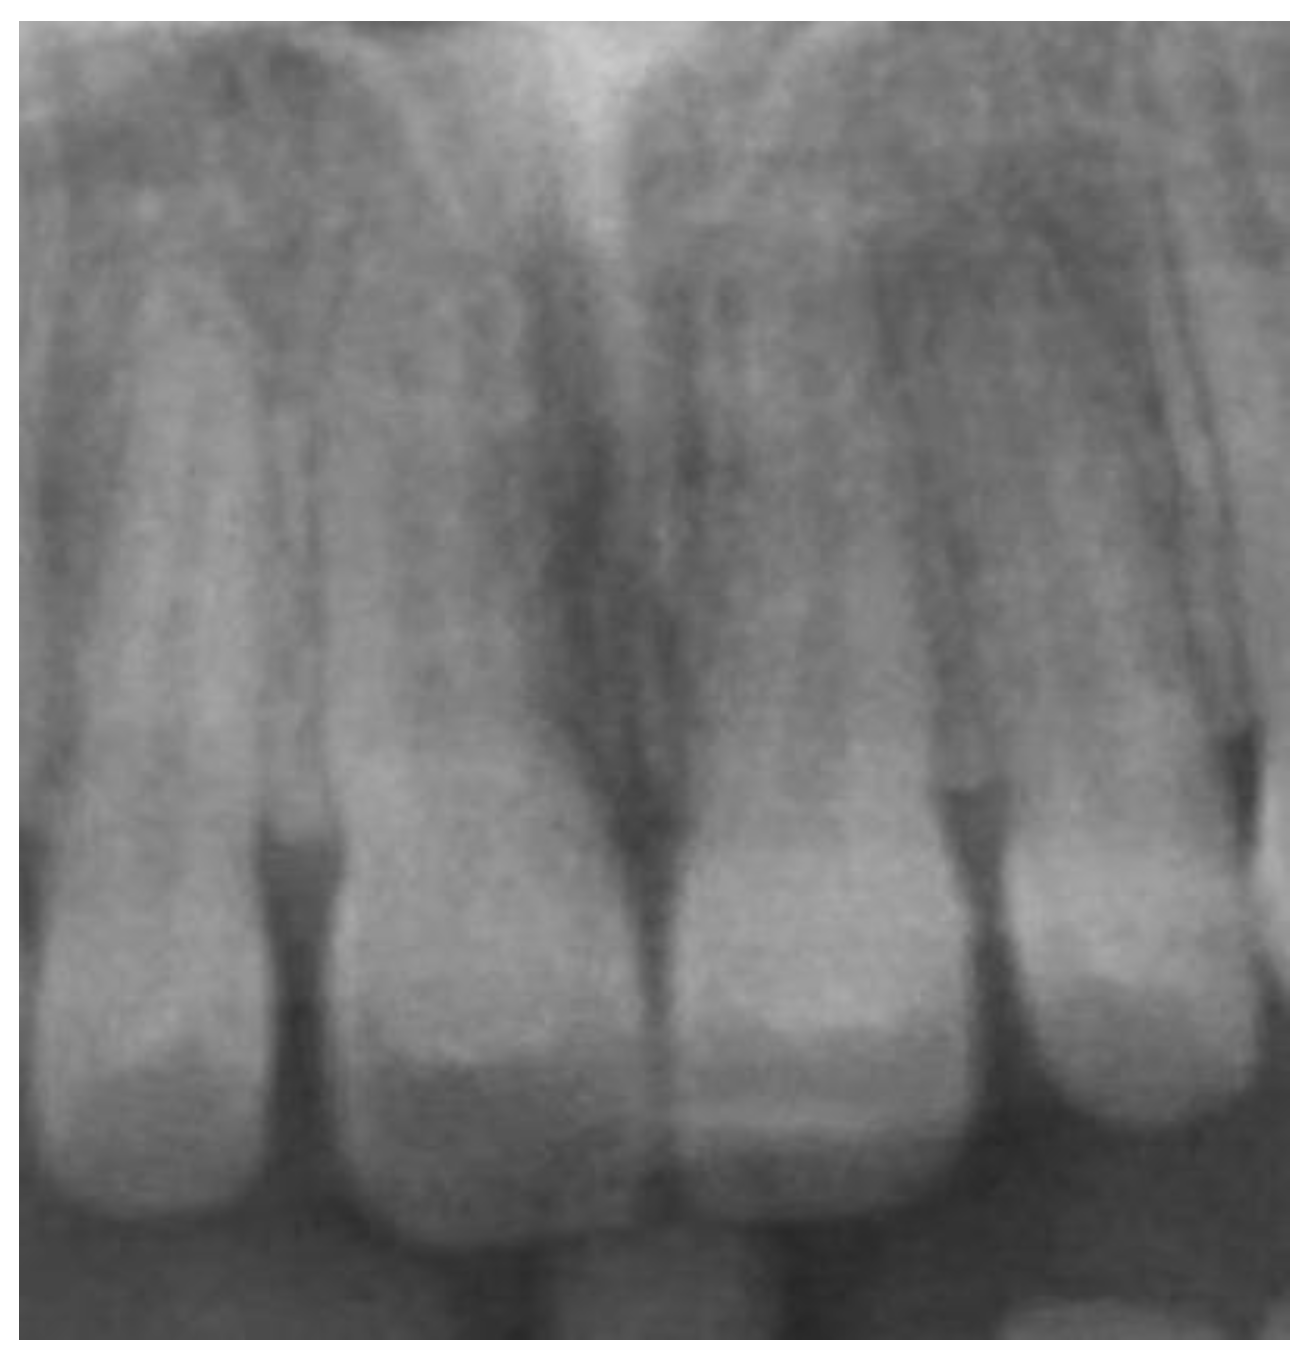

- Complete development of the upper incisor roots.

- Patients with permanent dentition.